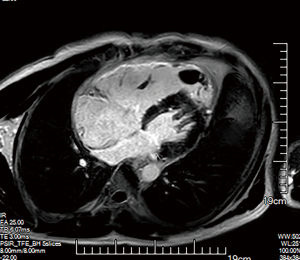

Electrocardiogram showed inverted T-waves and the Epsilon waves in leads V1–V3 (Figure 2). In view of the impaired cardiac function, we performed an echocardiogram (echo), which revealed a dilated right atrium (RA) at 59 mm × 65 mm, an expanded right ventricle (RV) at 31 mm × 37 mm with dysfunction (Figure 3A), the right ventricle outflow tract (RVOT) in parasternal short-axis view at 38 mm (Figure 3B), severe tricuspid regurgitation covering an area of 11.4 cm2, tricuspid annular plane systolic excursion (TAPSE) 13 mm and left ventricular ejection fraction (LVEF) 56% (Figure 3C). There was a pedicled mass about 26 mm × 16 mm in the apex of the RV (Figure 4A). Contrast echocardiography of the right heart was performed to define the nature of the mass, which showed that the microbubbles were not filled with the mass (Figure 4B). We also used real-time echocardiographic 3-dimensional (3D) imaging to observe the morphology of the mass (Figure 4C). Given the positive D-dimer and RA and RV dilation, we further examined the coagulation indices, arterial oxygen saturation, and lower-limb compression (through ultrasonography) to preliminarily rule out acute pulmonary embolism (PE). All the tests were negative. According to the recommendations of the European Society of Cardiology (ESC) Task Force for the diagnosis and management of acute PE (5), we considered that the patient had no predisposing factors for PE, and rather that they fulfilled the exclusion criteria for it. Based on these findings, we suspected that he was experiencing ARVC with right ventricular thrombosis, as he met 4 major criteria out of the 2010 revised Task Force criteria. The 4 major criteria for diagnosis are as follows: (I) severe dilation and dyskinesia of RV; (II) inverted T waves in leads V1–V3; (III) Epsilon wave in leads V1–V3; (IV) unsustained ventricular tachycardia of left bundle-branch morphology (6). To confirm the diagnosis, the patient underwent cardiac magnetic resonance (CMR) imaging. It was revealed that the left atrium and left ventricle were normal in morphology and function, but the RA and RV were significantly enlarged with dyskinesia. The RA was enlarged to 56 mm, the RV was enlarged to 47 mm, and the right ventricular wall was significantly thinner. The RV ejection fraction was 10%, the RV end-systolic volume was 187 mL, end-diastolic volume was 208 mL, and stroke output was 21 mL. The RV end-diastolic volume index (RVEDVI) was 115.7 mL/m2. The RV apex showed “shallow lobulated” changes with unclear demarcation from subepicardial fat, and diffuse strip-shaped abnormal enhancement shadows were observed under the endocardial wall of the right ventricular wall after delayed scanning, which was thought to be due to replacement of myocardial tissue by fibrous adipose tissue. After enhanced scanning, irregular low-signal filling defects were observed in the right ventricular apex, which was considered a sign of thrombosis. The above phenomena increased our certainty that the patient had ARVC with thrombosis (Figure 5). Since ARVC is rarely associated with thrombosis, we were interested to further study genetic relationship of this thrombosis. Unfortunately, the patient refused undergo the relevant genetic testing. We then gave the patient oral rivaroxaban 15 mg once a day as empiric anticoagulation to further confirm thrombus formation and prevent a embolic complications. Furthermore, we kept the patient on sotalol to control his arrhythmias and improve his outcome. An echo obtained 10 days later showed that the thrombus had significantly reduced to a size of 11 mm × 6 mm. This helped us to more clearly identify the presence of a thrombus, and that rivaroxaban had had a good treatment effect. Repeat echocardiography after about 4 weeks of sufficient anticoagulation indicated complete disappearance of the RV thrombus (Figure 6). Afterwards, an ICD was installed as secondary prevention of SCD.